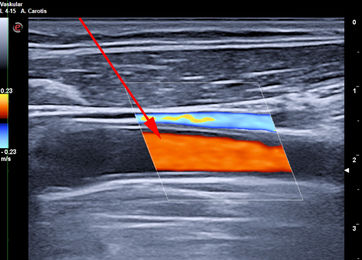

Goldstandard ist die Punktion der rechten Vena jugularis/anonyma supraklavikulär nach oder unter sonographischer Kontrolle. Die Sonographie muß Lagevarietäten klären und Thrombosen nach früherer Katheterisierung ausschließen.

Die Vena jugularis/ Vena anonyma kann nach Yoffa zwischen medialem und lateralem Kopf des Musculus sternocleidomastoideus von ventral punktiert werden oder horizontal von lateral. Diese Methode wurde 1972 von den amerikanischen Herzchirurgen Garcia, Mispireta und Pinho nach ausführlichen anatomischen Präparationen als einfachster und ungefährlichster Zugang beschrieben. Das Zielgebiet, der Zusammenfluß von Vena jugularis und Vena subclavia zur Vena anonyma ist so groß, dass die Punktion auch ohne Sonographie immer beim ersten Stich gelingt.

Die Punktion von ventral kann unter realtime Sonographie mit einem Standardschallkopf wegen des geringen Abstands zur Clavicula nur in der kurzen Schallachse erfolgen, wobei die Nadel nur abschnittsweise sichtbar ist. Mit dem kleinen 22 MHz Fingerschallkopf aus der Rheumatologie ist auch eine Punktion in der langen Schallachse möglich.

Die in der Anästhesie verbreitete Punktion der distalen Vena jugularis ist komplikationsträchtig und sollte vermieden werden. Normalerweise liegt die Vena jugularis lateral der A. carotis.

Bei der schädelnahen Punktion muß der Kopf nach links gedreht werden, weil sonst das Kinn im Weg ist. Dadurch rotiert die Vene vor die Arterie und das Lumen wird schlitzförmig.